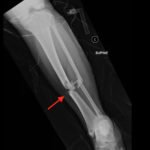

Plain film shows severely comminuted and displaced mid tibia/fibula fractures of bilateral lower extremities (red arrows) and comminuted right fibular head (blue arrow) and proximal shaft fracture (yellow arrow).